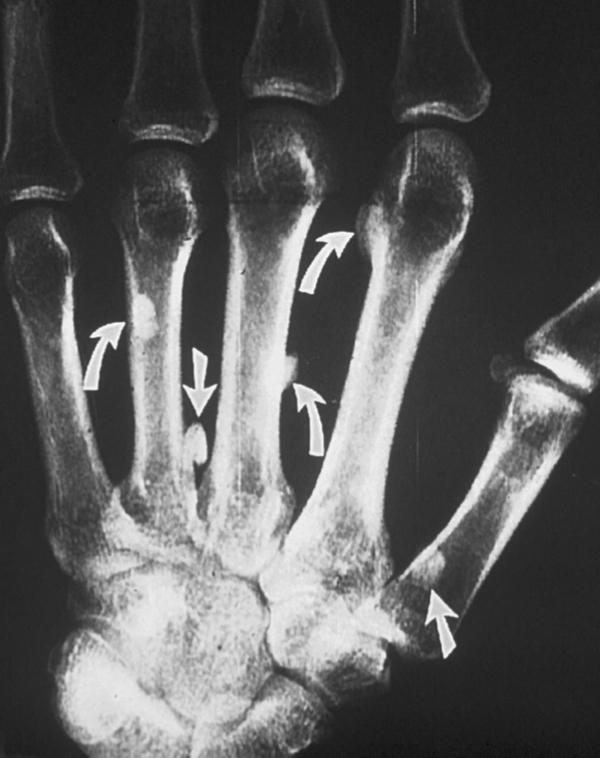

what is this?

what is the triad associated with it?

Gardner Syndrome

well efined

opaque

clean borders